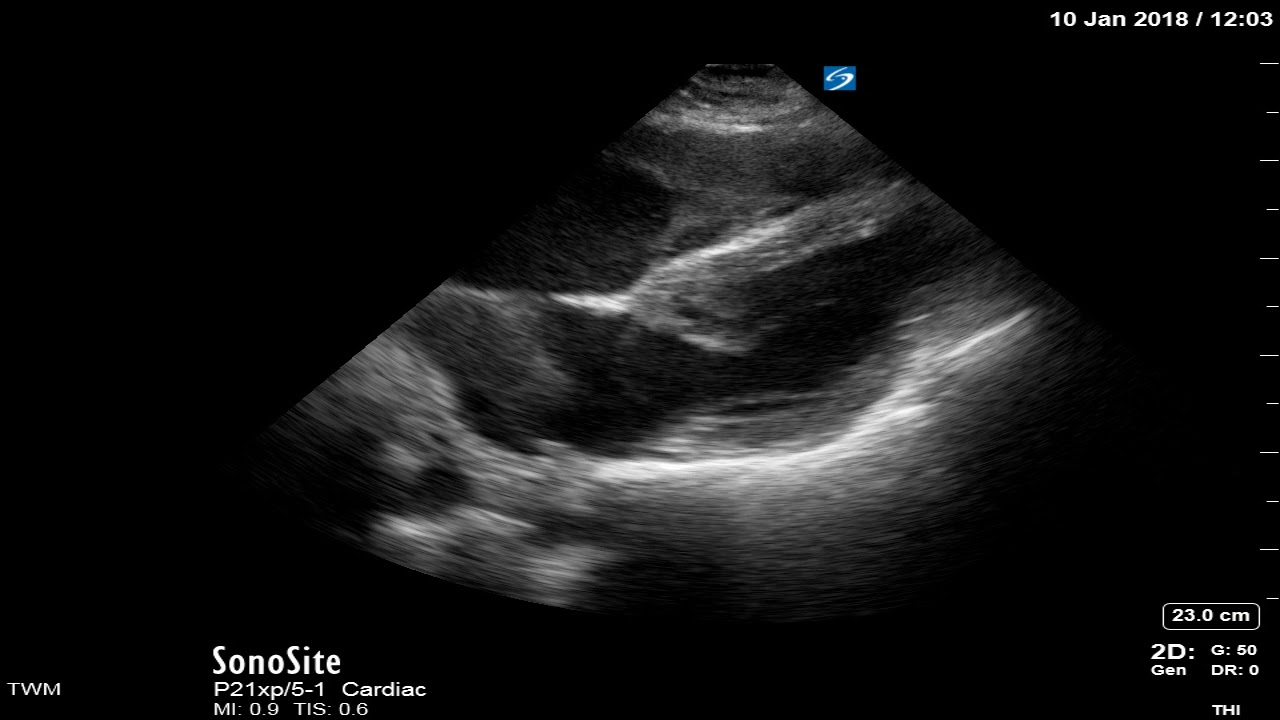

Use of Ultrasound in Cardiac Arrest EM Ultrasound Section Cardiac Standstill Asystole is cardiac standstill with no cardiac output and no ventricular depolarization, as shown in the image below; When your heart stops pumping blood, you become unconscious. Cardiac standstill, also known as true asystole, is defined as the complete. Sudden cardiac arrest (sca) is the sudden loss of all heart activity due to an irregular heart rhythm. Cardiac arrest happens. Cardiac Standstill.

Cardiac Standstill POCUS RK.MD Cardiac Standstill That means you don’t have a heartbeat. Cardiac standstill, also known as true asystole, is defined as the complete. Asystole is cardiac standstill with no cardiac output and no ventricular depolarization, as shown in the image below; When your heart stops pumping blood, you become unconscious. Sudden cardiac arrest (sca) is the sudden loss of all heart activity due to. Cardiac Standstill.